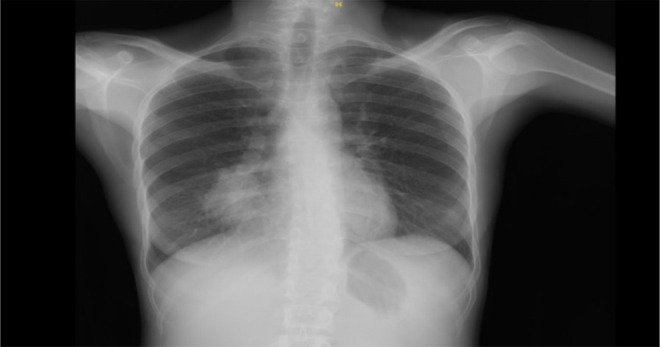

Echinococcus granulosus remains a global public health issue. Although predominantly affecting the liver, the lungs are the second most affected organ and often undergo surgical intervention. Here, a case managed by bronchoscopy and medical therapy is presented. A 26-year-old woman was presented with a cough, hemoptysis, and a 5 kg weight loss in the last two months. Chest imaging identified a 4 cm centrally cystic mass lesion in the middle lobe of the right lung, which was suspicious of lung cancer. Bronchoscopy revealed a whitish, plastic-like object that was difficult to extricate and obstructed the middle lobe bronchus. We removed the material and purulent secretions covering it and opened the middle lobe bronchus totally. The histopathological study verified its consistency with hydatid cyst. There was no evidence of a hydatid cyst on computerized thomography after bronchoscopy. The lesion in the left lobe of the liver, confirmed to be suggestive of a hydatid cyst via ultrasonography, was treated using the PAIR technique. We administered oral albendazole to continue the treatment. It may be a reasonable approach to postpone surgery in order to preserve lung tissue in patients who have undergone complete removal of hydatid cyst material via bronchoscope.